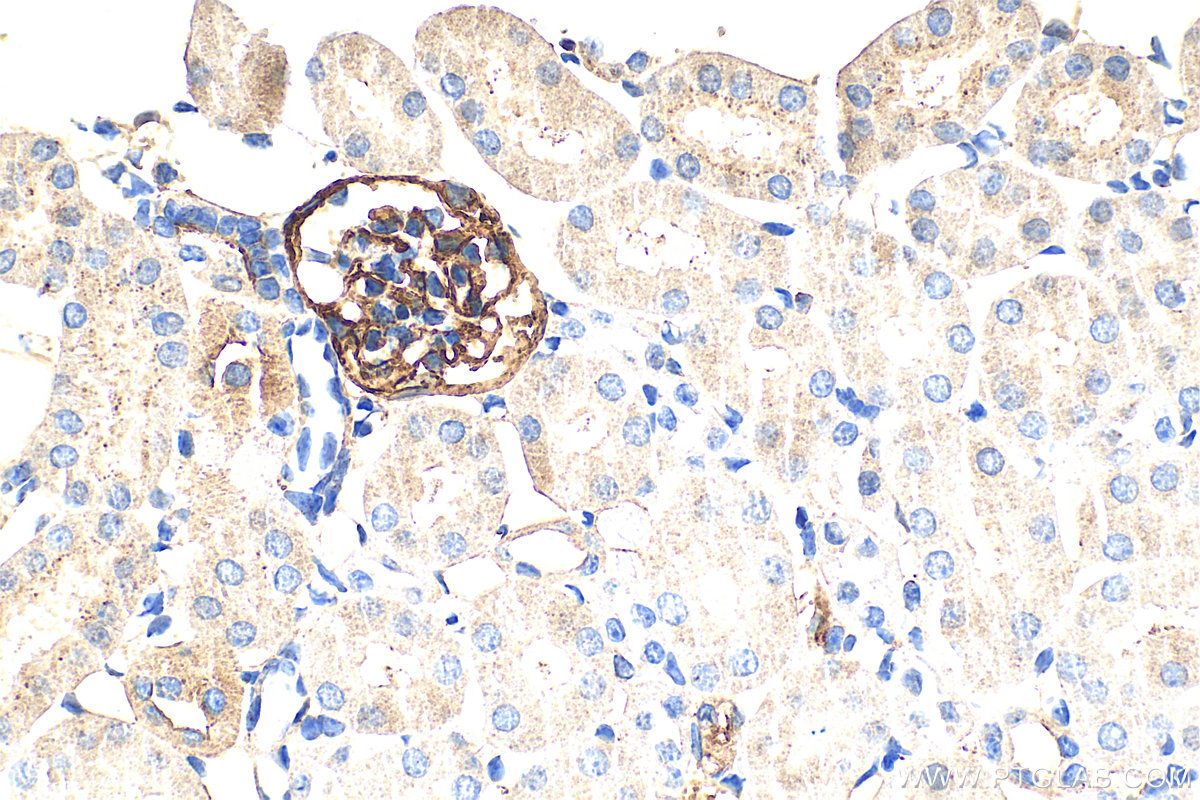

| Positive IHC detected in | mouse lung tissue, mouse kidney tissue Note: suggested antigen retrieval with TE buffer pH 9.0; (*) Alternatively, antigen retrieval may be performed with citrate buffer pH 6.0 |

| Immunohistochemistry (IHC) | IHC : 1:400-1:1600 |

33099-1-AP targets Podoplanin in WB, IHC, ELISA applications and shows reactivity with mouse samples.

Podoplanin was identified as a glycoprotein found in the cell membranes of glomerular epithelial cells (podocyte) (PMID: 9327748). It is a lymphatic marker because the expression of podoplanin has been detected in lymphatic but not blood vascular endothelium, and is useful as the marker of tumor-associated Lymphangiogenesis. Podoplanin has a function in developing testis, most likely at the level of cell-cell interactions among pre-meiotic germ cells and immature Sertoli cells. It may be involved in cell migration and/or actin cytoskeleton organization. When expressed in keratinocytes, PDPN induces changes in cell morphology with transfected cells showing an elongated shape, numerous membrane protrusions, major reorganization of the actin cytoskeleton, increased motility and decreased cell adhesion. It is required for normal lung cell proliferation and alveolus formation at birth. PDPN induces platelet aggregation. It does not have any effect on folic acid or amino acid transport and does not function as a water channel or as a regulator of aquaporin-type water channels.